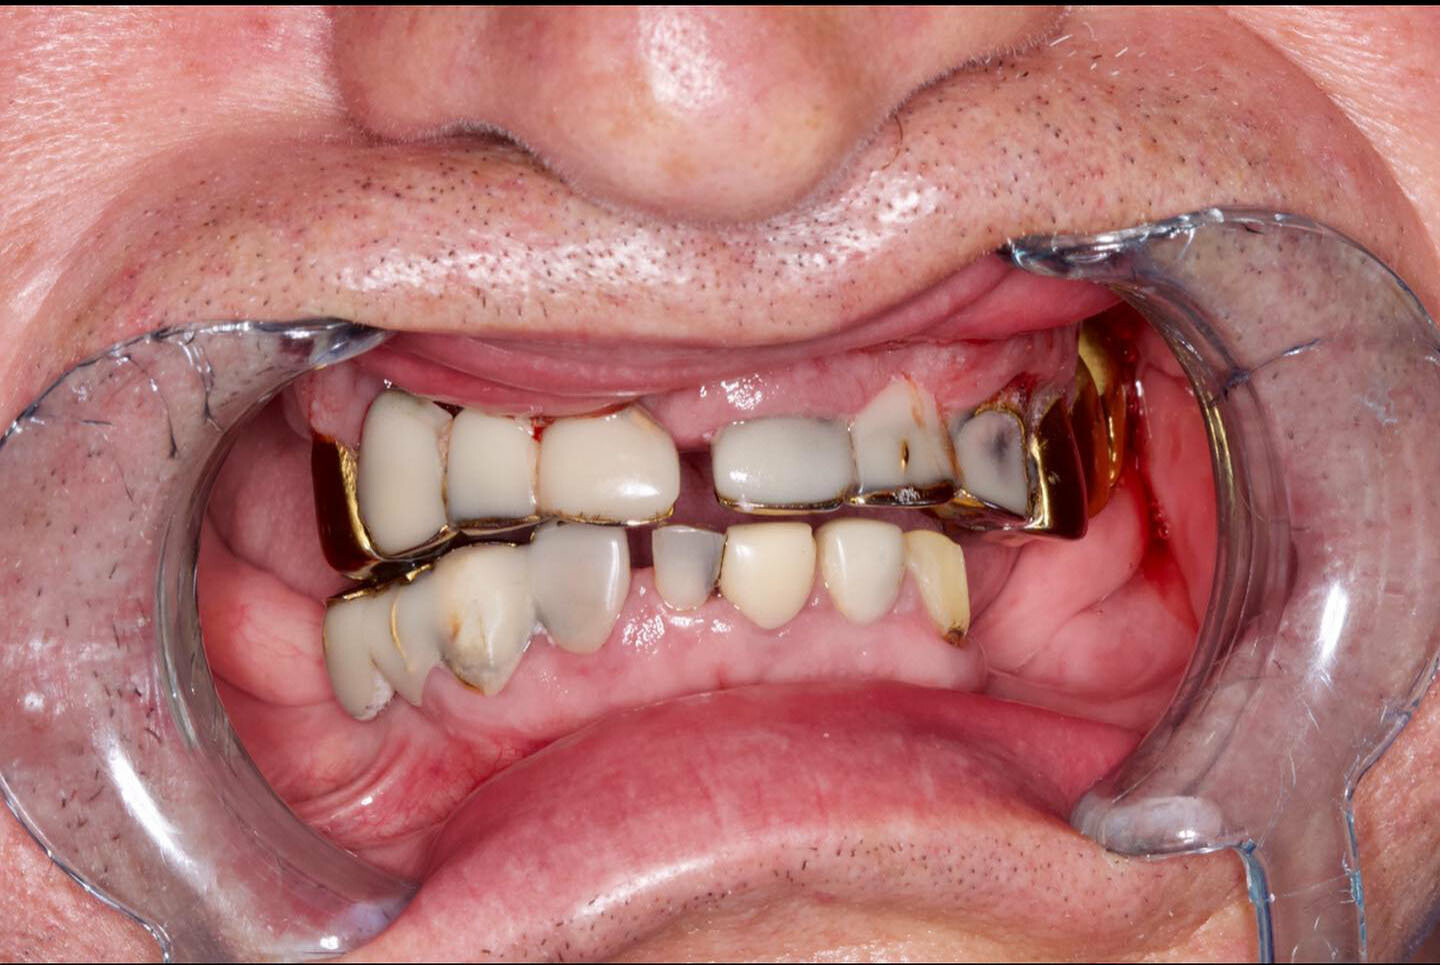

All-on-4 («все на четырех») - прогрессивный протокол имплантации челюсти на 4 имплантах, применяющийся для протезирования зубного ряда при его значительных дефектах (когда утрачено множество зубов) или в случае полной адентии. Начало методике было положено более 20 лет назад, когда первые попытки португальского врача П. Мало в данном направлении увенчались успехом. В имплантации All on 4 непревзойденный комфорт для пациента дополняется другим, не менее значимым аспектом – доступной стоимостью протезирования. |